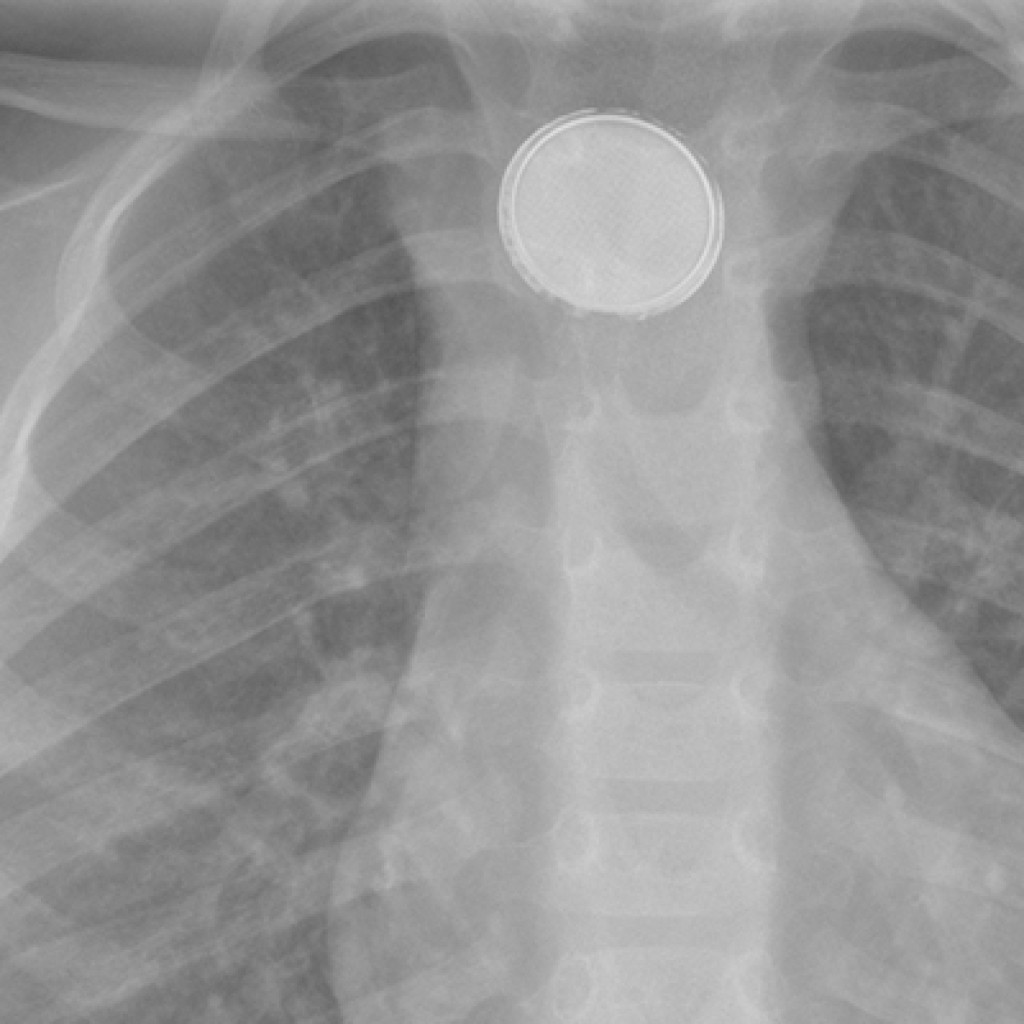

Wat zijn de risicofactoren voor een gecompliceerd beloop bij inname van een batterij bij jonge kinderen? In de meeste gevallen passeert de batterij spontaan het maag-darmkanaal. Laat toch altijd laagdrempelig röntgendiagnostiek verrichten om een goede risico-inschatting te kunnen maken.